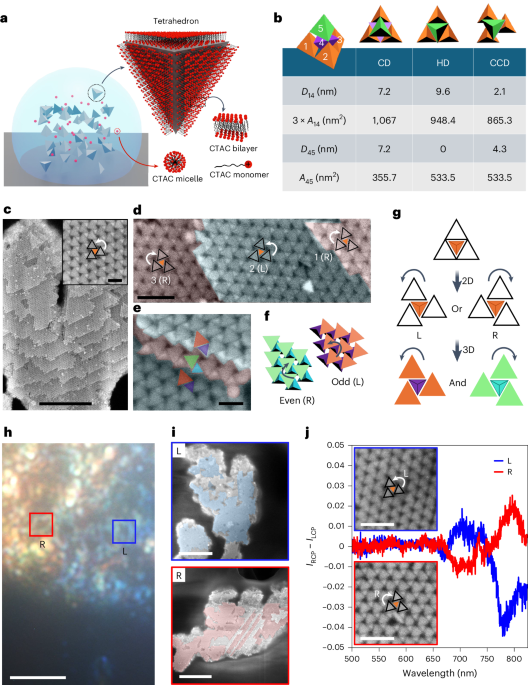

The DICOM data of CT colonography were used to create a large-scale database, design an AI algorithm, and perform validation. To protect patient privacy, only image data, lesion information, sex, CT device (multidetector CT with at least 16 rows), slice thickness, and imaging position were used. The Strengthening the Reporting of Observational Studies in Epidemiology guidelines were followed during this study (Fig. 1). The research period spanned from October 2019 to August 2023, and the DICOM data used as training data were collected prior to this period. These data included screening tests from a multicenter joint trial conducted in Japan to validate the accuracy of CT colonography (Japanese National CT Colonography Trial) [15], data from another multicenter joint trial aimed at reducing the dose of intestinal cleansing agents while validating accuracy (Reduced-Laxative CT Colonography Trial) [16], and clinical data from Saitama Prefectural Cancer Center (Saitama) and Tonan Hospital (Tonan). The collected data were randomly divided into training and validation datasets. Table 1 shows the breakdown of the training data, including patient information, CT equipment used, and lesion size. During the present study, images obtained in one position were defined as one CT series; however, many images were obtained in two positions. In this study, we adopted the criteria used in previous research and defined lesions measuring 6 mm or larger as target lesions [3, 17]. Specifically, all target lesions were lesions ≥ 6 mm, and we categorized them into two groups: 6–10 mm and ≥ 10 mm. In most cases, the slice thickness was ≤1.0 mm. Although lesions ≥6 mm were included as targets in this study, the majority measured ≥10 mm. All lesions were pathologically confirmed to be adenomas or adenocarcinomas.

Study overview. The number of patients and series are shown for the AI training dataset and the external validation dataset, which were obtained from different institutes. The differences between the number of patients and the number of series are attributable to the fact that two CT examinations were performed per patient in two positions. AI: artificial intelligence; CT: computed tomography; JANCT: Japanese national CT colonography trial15; RCTC Trial: reduced-laxative CT colonography trial16.

Fig. 1 shows the numbers of patients and CT series in the AI learning dataset (training dataset and internal validation dataset) and external validation dataset. The AI learning datasets collected from the two previously published multicenter trials performed in Japan and the two aforementioned facilities were randomly divided into a training dataset used for AI training and an internal validation dataset that was used to validate the training results and there were no cases in each dataset that have been analyzed more than once. The external validation datasets of the two facilities of Fukushima Medical University Aizu Medical Center (Aizu) and Nagasaki Kamigoto Hospital (Kamigoto) were not used for AI learning.